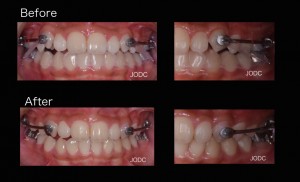

顎間ゴムをかけることで上顎は後方へ、下顎は前方へ誘導される力がかかります。この作用で上下顎の顎関係の改善をはかります(After写真は約1ヶ月後)。

犬歯から第一大臼歯にかけて遠心移動し、上下顎がしっかり咬み合う所まで誘導できました。カリエールを装着する事で後の矯正治療で行うブラケット装置での治療期間を短縮することができます。